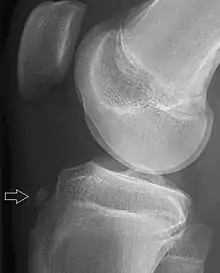

| Avulsion fracture of the proximal middle phalanx on the palm side | |